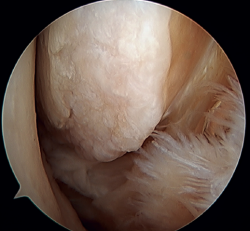

Otro punto de interés es la presencia de os subfibularis; en estos casos, existe la opción de la fijación, si bien no suele ser factible y la mejor opción terapéutica es su exéresis y reconstrucción, debido a la imposibilidad de realizar una reparación directa(60) (Figura 4).

Tratamiento artroscópico de la inestabilidad rotacional/multidireccional

La inestabilidad rotacional es un concepto relativamente novedoso descrito en 2011 por Buchhorn(67), donde se describen lesiones combinadas del complejo lateral y del ligamento deltoideo, y una técnica de reconstrucción anatómica para ambas lesiones. Aunque no existe evidencia biomecánica de por qué se produce la lesión medial en pacientes que no han sufrido traumatismos en eversión, probablemente el estrés mantenido sobre el complejo medial en la inestabilidad lateral puede evolucionar a una inestabilidad rotacional, lo cual va en línea con la teoría del efecto dominó previamente explicada(5,62). Se estima que hasta el 10-15% de las ICLT pueden evolucionar a la lesión del complejo medial, afectando especialmente sus fibras más anteriores. Recientemente, Vega(68) describe la combinación de lesiones del complejo lateral con la lesión en “hoja de libro” (Figura 7) del fascículo tibiotalar superficial del ligamento deltoideo debido a la excesiva rotación interna en la inestabilidad lateral crónica, así como su tratamiento mediante reparación directa de ambas lesiones. Acevedo(34) y Vega(68) también describen la posición de seguridad de los anclajes en el maléolo medial.